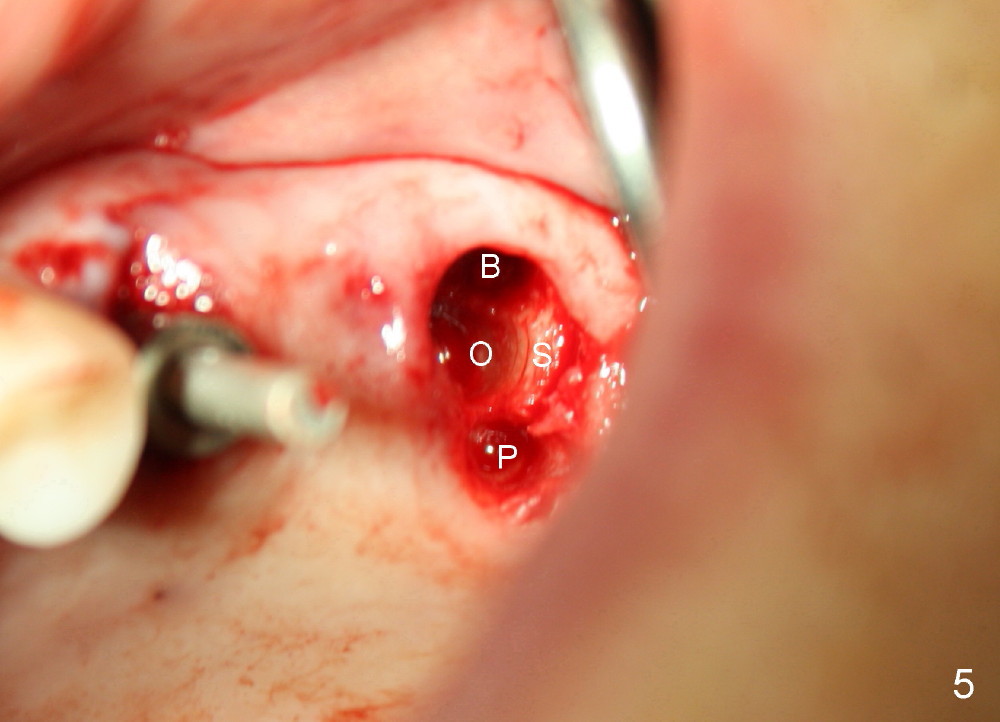

A 84-year-old man has a failing bridge.  A short implant was placed at the pontic site 5 months ago (Fig.1, taken 2 months postop).  The bridge was temporarily recemented.  It is planned at next appointment to extract #13, uncover the implant at pontic and save #15 if possible.  When the bridge is removed, the tooth #15 is also found non salvageable (Fig.2). The root stump of #15 is oval, 5x10 mm.  Preop PA shows that the 2nd molar has two roots (Fig.1: *).  When the tooth is extracted, the septum is found wide buccolingually (Fig.3: S, between the buccal (B) and palatal (P) sockets).  Osteotomy is formed in the septum with combination of drills and osteotomes, followed by insertion of taps (Fig.4).  Finally the osteotomy (Fig.5 O) in the septum (S) of #15 deviates into the buccal (B) socket.  When the implant is placed (Fig.6), it deviates buccally slightly (Fig.7).  The remaining sockets are filled by bone graft (Fig.7 G).  Immediate provisional bridge is fabricated after placement of abutments (A).  The main purpose of the provisional at early stage is to hold bone graft in place.  There is no occlusal contact with the opposing dentition,  Due to time constraint, the uncovering of #14 is postponed.  The provisional dislodges 2-3 days postop.  The patient returns for recementation 5 days postop; the sockets have initially healed (Fig.8,9, as compared to Fig.7).